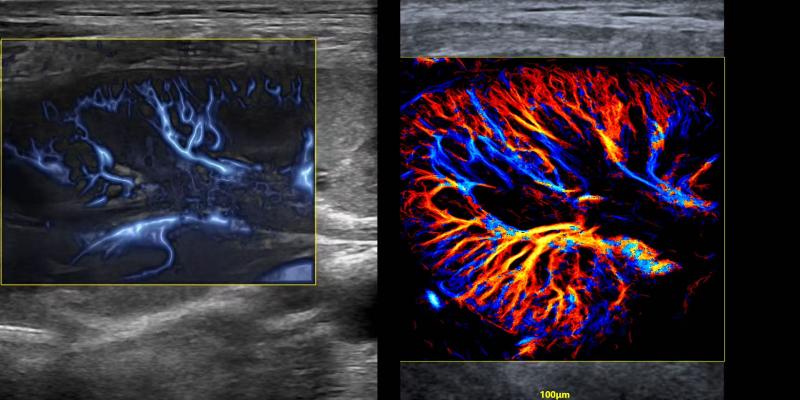

2024年、飛依諾はURM超高解像度の顕微畫(huà)像技術(shù)を開(kāi)発したことを発表した。この技術(shù)は臨床と科學(xué)研究活動(dòng)にかつてない真新しい超音波の視野を切り開(kāi)き、業(yè)界の専門(mén)家から「今後10年間に超音波業(yè)界で最も重要な技術(shù)的突破」と評(píng)価された。

現(xiàn)在、全國(guó)で100以上の三甲病院がこの製品を使用して臨床研究を行っている。さらに、ヨーロッパ、南米、アジアなど世界各地からのトップクラスの専門(mén)家は飛依諾と協(xié)力して関連する科學(xué)研究も行っている。